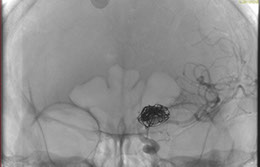

La paciente ingreso al Servicio de Hemodinamia el día martes 11 de febrero con un aneurisma cerebral gigante en la carótida izquierda y se le practicó una embolización; es decir una oclusión por dentro del mismo, donde se colocó un dispositivo denominado coils más un stent diversor de flujo. El procedimiento fue exitoso y contó con la colaboración de médicos neurointervencionistas del Instituto Oulton de la Ciudad de Córdoba.